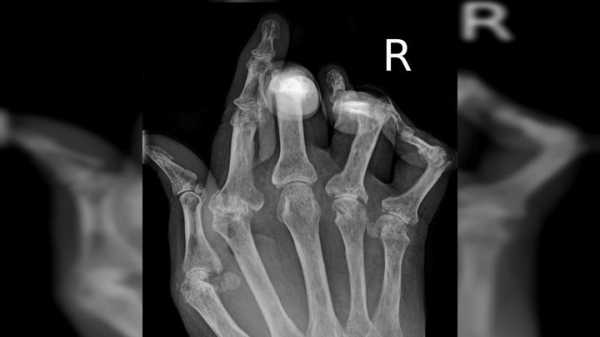

Рентгеновский снимок кисти, поражённой ревматоидным артритом.